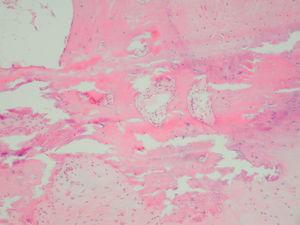

Se realizó toma de biopsia incisional en polo superior de hélix demostrándose en el estudio anatomopatológico degeneración fibrilar del cartílago, áreas de calcificación y metaplasia ósea (fig. 2). En la analítica general, que incluyó calcio, fósforo, fosfatasa alcalina, hormona paratiroidea y cortisol basal, no se observaron alteraciones.

Fig. 2.--Biopsia auricular que muestra metaplasia ósea. (Hematoxilina-eosina, x200.)